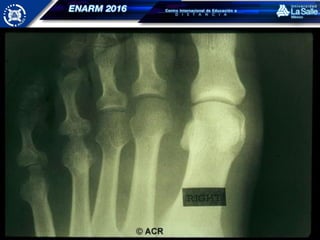

RADIOLOGÍA

Radiología simple - convencional

CAMBIOS RADIOLÓGICOS

Aumento de volumen de los tejidos blandos,

fusiforme y generalmente simétrico

Osteopenia yuxtaarticular

Disminución simétrica del espacio articular

Erosiones marginales del hueso subcondral

Pérdida de la alineación

Deformidades

ARTRITIS REUMATOIDE RADIOLOGÍA Radiología simple- convencional Ultrasonido TC IRM Artrografía

• 57.

ARTRITIS REUMATOIDE CAMBIOS RADIOLÓGICOS Aumentode volumen de los tejidos blandos, fusiforme y generalmente simétrico Osteopenia yuxtaarticular Disminución simétrica del espacio articular Erosiones marginales del hueso subcondral Pérdida de la alineación Deformidades